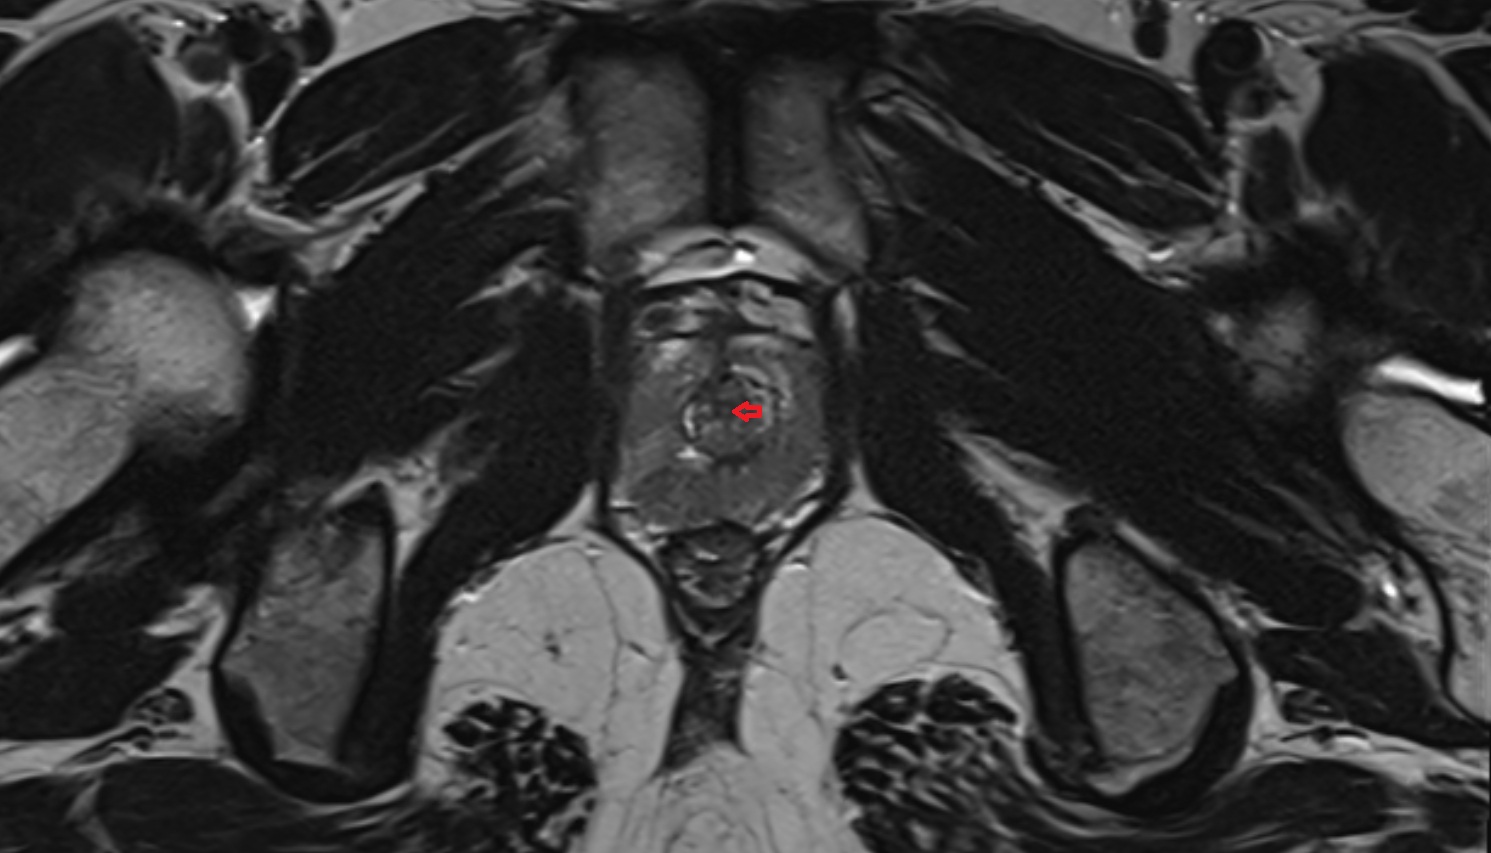

- Peripheral zone of prostate

- Anterior Fibromuscular Stroma of prostate

- Central zone of prostate

- Transitional zone of prostate